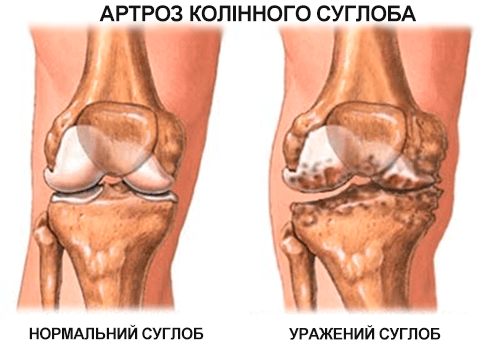

Зубицька: "Секрет - в розумінні причини хвороби. Взагалі в енциклопедіях налічують до 147 можливих причин розвитку остеохондрозу і артрозу, але дослідження знайшли одне - суглоби, хребці і хрящі втрачають свою еластичність, звідси і біль. Вони зношуються через погане кровопостачання.

Зубицька: "Це означає, що середньовічна медицина йде в минуле і ви зможете вилікувати свої захворювання в домашніх умовах за місяць-два. «Пантогор» не заморожує, не знеболює, він "перезапускає ". Усуває причину смого болю і повертає суглоби, хребет в нормальний стан. Хворий не просто позбавляється симптомів, а вирішує основну проблему - ослаблене повільними, старими клітинами, кровопостачання хрящів.